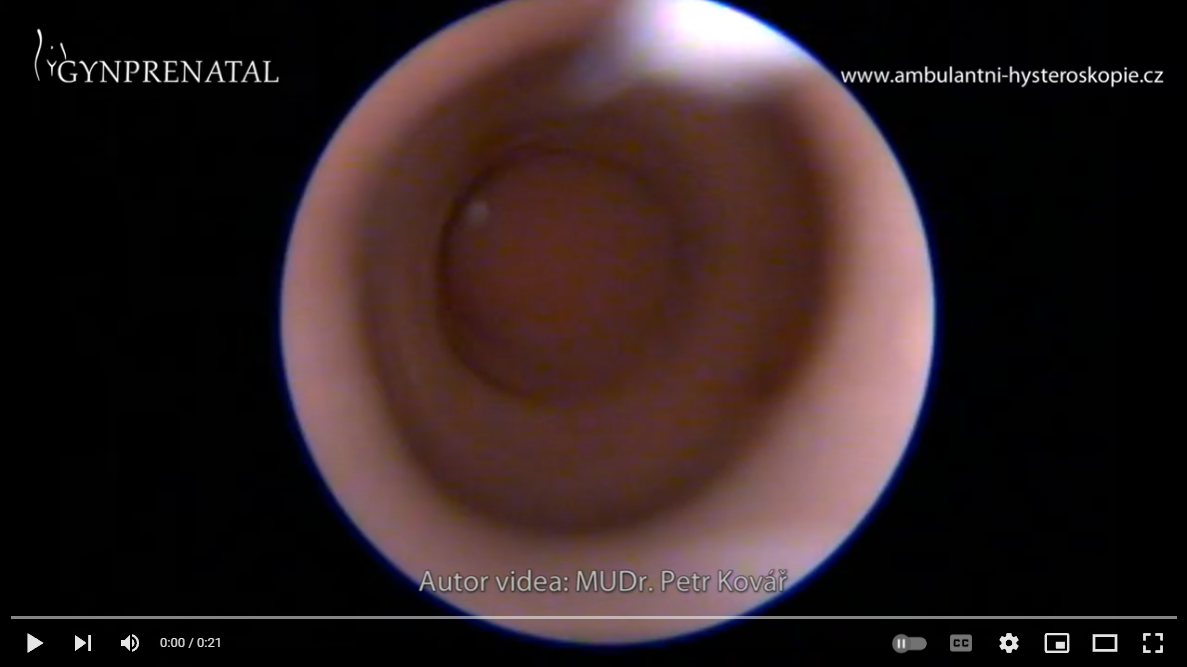

Uterus bicornis s hematometrou

Uterus septus s hematometrou

Mukometra polyp

Mukometra + synechie